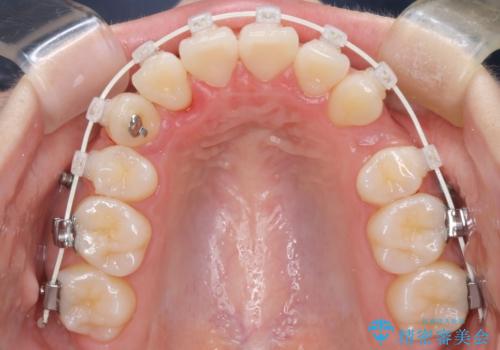

- 4番の歯を4本抜歯をし、上顎にマイクロインプラントを2本埋入し、遠心移動を行いました。

主訴のオープンバイトは改善し、抜歯をしたことで前歯が下がり綺麗になりました。抜歯矯正でしたが1年2か月という短い期間で終了しました。